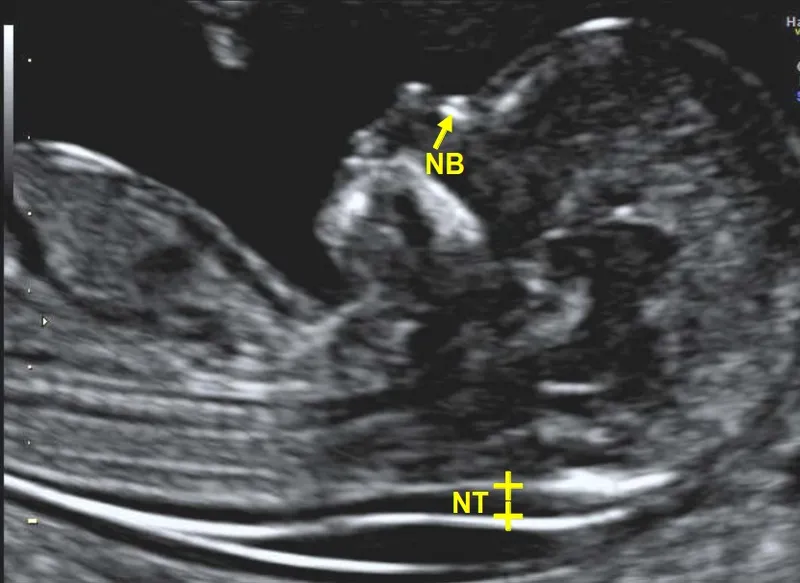

Nuchal Translucency (NT) on Ultrasound

- Measures subcutaneous fluid at the back of the fetal neck.

- ↑ NT suggests increased risk for aneuploidies (Trisomy 21, 18) and cardiac defects.